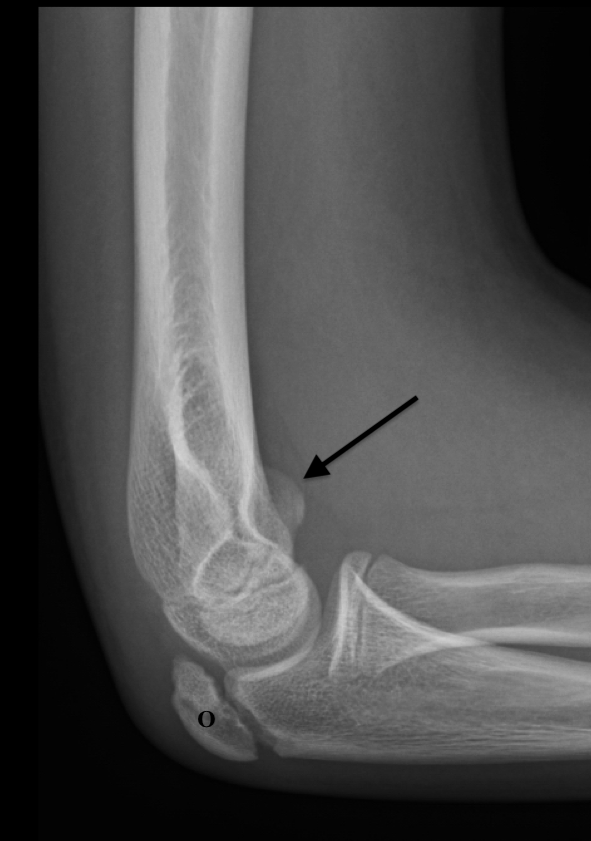

Figure 7A: Lateral view with markings. This shows the ossification center of the olecranon (O). Also note the probable anterior displacement, presumably of the medial epicondyle (arrow).